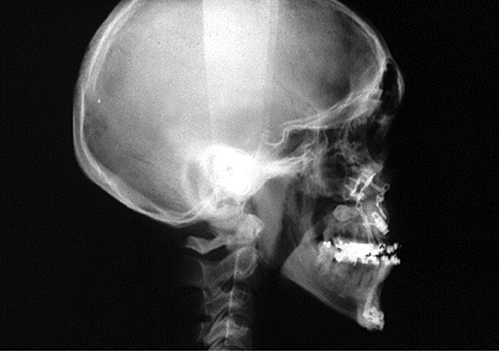

Figure 2: Demonstration of changes to posterior airway space by maxillary

advancement osteotomies. Preoperative (top) postoperative (bottom).

It has become increasingly recognised that carrying out mandibular and maxillary osteotomies can also have a profound positive or negative effect on the posterior airway space at both the level of the tongue base and the palate, which is predictable and dependent on the direction of movement. By advancing the mandible and the maxilla 8-10mm especially in combination with an advancement genioplasty the posterior airway space can be greatly improved. This has been measured on lateral cephalometric radiographs and more recently 3D computerised tomography (CT) has demonstrated the increased airway volume achieved [6]. More importantly than radiographic appearance, however, is the resolution in symptoms of OSA and demonstrable improvement in polysomnography studies. It is becoming increasingly recognised that orthognathic mandibular setback surgery can lead to conversion into OSA [7].